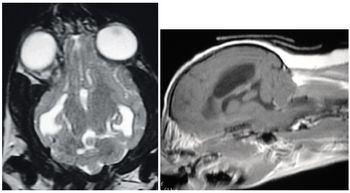

In contemporary veterinary medicine, magnetic resonance imaging (MRI) is an important tool in the diagnosis of neurological problems.

Cleveland ? Universal Medical Systems Inc.'s Vet-MR Grande?, the first dedicated dual-purpose magnetic resonance imaging (MRI) system for all small and large animals, was unveiled at the North American Veterinary Conference (NAVC).

Hypertensive encephalopathy (HyE) is an acute neurological syndrome, which can be characterized by any of the following clinical signs: nausea, vomiting, abnormal vocalization, ataxia, tremors, photophobia, blindness, frequent blinking, head pressing, stupor and/or seizure activity.